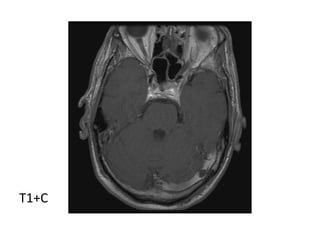

Enhancing infarcts , T1+C shows gyriform enhancement at the left insula and

posterior parietal lobe from a subacute left MCA infarct

Enhancing infarcts , T1+C shows gyriform enhancement at the

left insula and posterior parietal lobe from a subacute left

MCA infarct